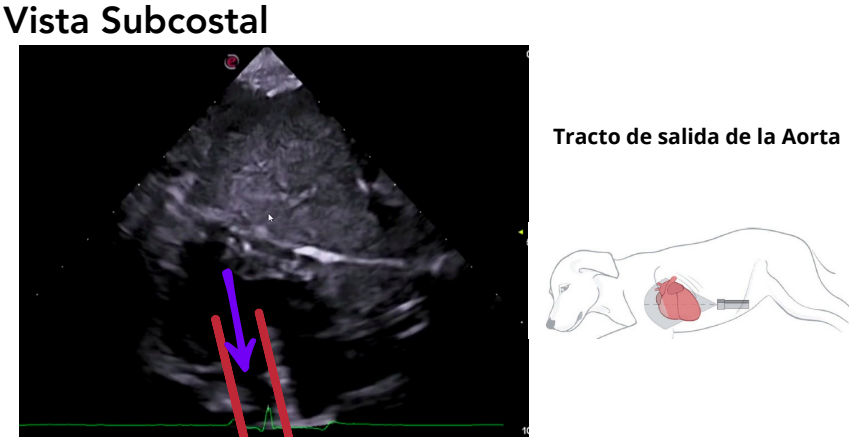

Vista subcostal (subxifoidea)

- Se accede a través de la apófisis xifoides.

- Se usa un transductor de baja frecuencia (2–2.5 MHz).

- Permite estudiar el tracto de salida del VI y la aorta ascendente.

- Alineación ideal para el Doppler, que mide velocidades en aorta.

Valores normales:

- 1.1–1.5 m/s (normal)

- >3 m/s: estenosis aórtica

- <1 m/s: CMD